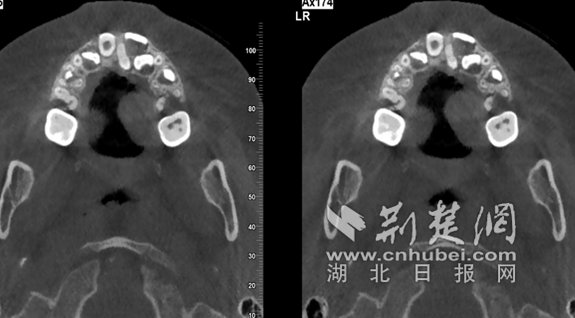

小丹的门牙迟迟未替换是因为一颗小小的多生牙横在了恒牙的上方 通讯员供图

经过口腔科程娟医生检查发现,小丹的门牙迟迟未替换是因为一颗小小的多生牙横在了恒牙的上方。只有将这颗多生牙拔除,新牙才能正常生长。“多生牙是指除了正常的乳牙和恒牙外,再长出的额外牙齿。常见于上门牙区,已经长出的多生牙相对容易辨别,通常呈锥形。但是,隐藏在骨头中的多生牙很难被发现,造成孩子迟迟不换牙。”在跟小丹爸爸耐心解释后,程医生为小丹进行了一次简单的拔牙手术后,小丹的恒牙终于可以开始正常萌出了。